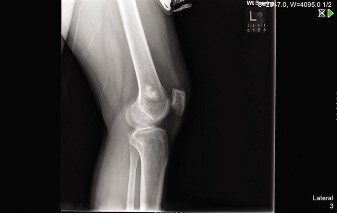

A 32-year-old male presented to the emergency department 1 hour after sustaining a fall while skateboarding. …